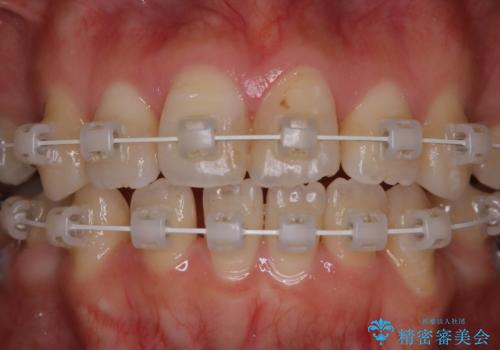

- ワイヤー矯正中のメンテナンスでPMTCを希望されました。染め出しを行い、歯ブラシ指導とPMTC30分コースを行いました。

この部分をしっかりと磨けるようになると、虫歯や歯周病を予防することができます。

矯正中にも、虫歯や歯周病予防をしっかり行うことが大切です。